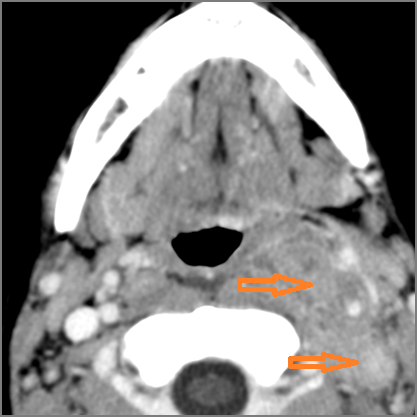

Cervical Lymph Nodes

There is reactive cervical lymphadenopathy. [Yes/No]

There is suppurative cervical lymphadenopathy. [Yes/No]

If there is suppurative cervical adenopathy the purulent material outside the lymph node(s) capsule(s). [Yes/No]